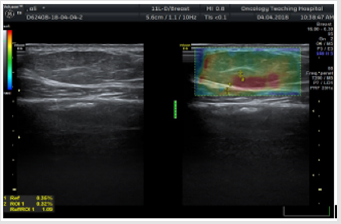

In this study: Fibroadenoma, simple cyst, and fibrocystic changes were the foremost common benign lesions whereas infiltrative ductal carcinoma was the foremost common malignant lesion. Fibroadenomas showed up smooth oval or adjusted in shape with well-defined edges, homogenous echotexture, isoechoic with bilateral acoustic shadowing, wider than taller and either softer than or had the same elasticity as adjoining glandular tissue with score 1, 2 or 3 (Figure 1). Fibroadenomas sometimes have size and stiffness pattern by elastography which is similar to that of malignant lesions as in calcified fibroadenomas with elasticity score 3 or 4 (Figure 2). Malignant breast lesions are speculated, irregularly formed, unwell outlined, with heterogeneous echotexture, distorted design, central shadowing, taller than wider, small calcifications, elastography score 4 or 5. They appeared larger on the elastography image due to higher visualization of the encircling desmoplastic reaction (Figures 3 & 4).

Figure 1: 36 year’s females with single left palpable breast lump.

a) The conventional US showed well-defined iso to the hypoechoic focal lesion

b) On elastography: the lesion showed a heterogeneous but mostly green color signature with elastography score 2. The diagnosis was confirmed by follow up after 6 months to be fibroadenomas.